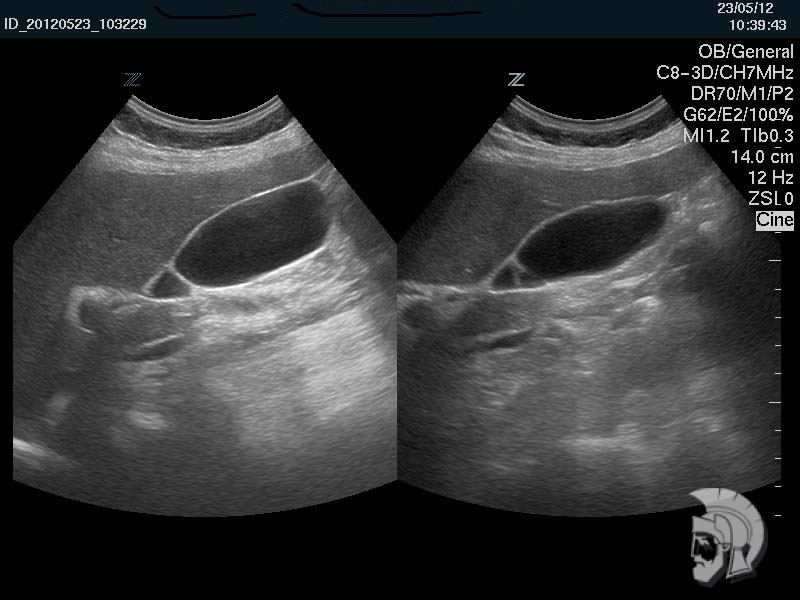

| Фото желчного пузыря. Перетяжка в нижней трети желчного пузыря мужчины 43 лет |